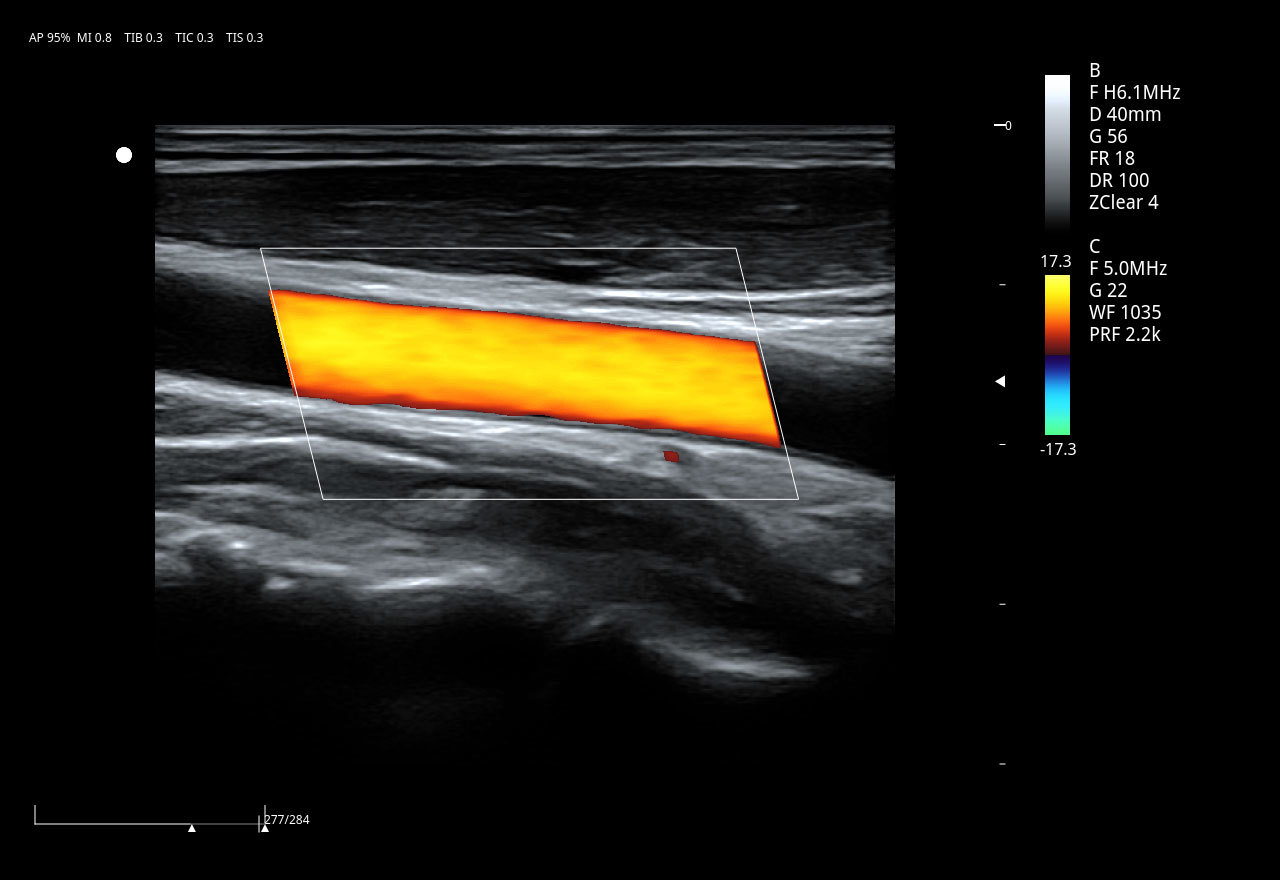

El Doppler Color ViV 20 es un ecógrafo de nueva generación diseñado para ofrecer una experiencia clínica superior con un equilibrio perfecto entre rendimiento, durabilidad y accesibilidad. Su arquitectura avanzada proporciona imágenes claras y precisas, permitiendo diagnósticos confiables en aplicaciones como abdomen, ginecología, vascular, partes blandas y más.

Imágenes clínicas extraordinarias

| Aplicaciones | Cardiología, abdomen, vasos sanguíneos, estudios generales |